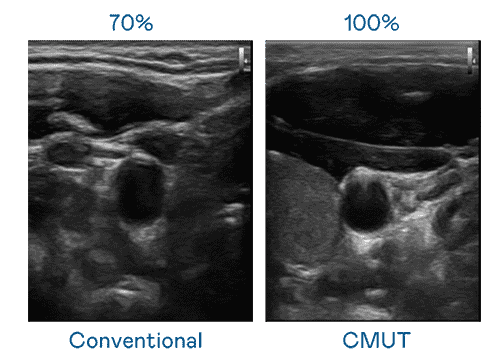

CMUT 技术是一种用电容式微机电元件来产生超音波讯号的技术。。。。与传统 PZT 压电式技术相比,,,,CMUT 频宽增加 30%,,,,更宽频的超音波讯号让影像解析度大幅提升,,,,是实现高影像品质医疗超音波扫描、、促进精准医疗发展的关键技术。。。。

大频宽带来超清晰影像

超音波影像的解析度高低,,,首先取决于探头能发出的讯号频宽。。尊龙集团 CMUT 可提供高清晰的超音波讯号,,提供高频宽、、高灵敏度、、、、影像纹理细节更高的超音波影像,,,,协助医护人员缩短影像判读时间及利用精准的医疗影像进行诊断。。。